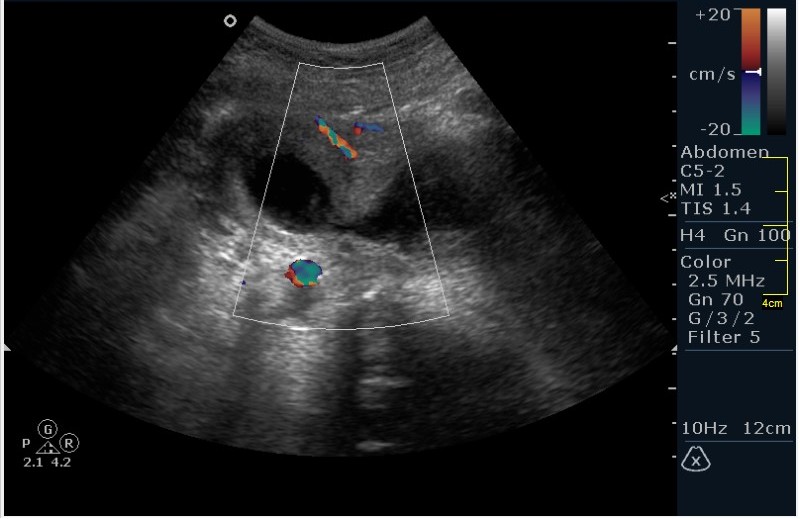

Девочка 12 лет; жалобы на частое мочеиспускание; тупые, тянущие боли в малом тазу. Менструацию отрицает. УЗИ малого таза, все сонограммы выполнены по средней линии, в поперечной и сагитальной проекциях.

Гематокольпос при заращении девственной плевы. Менархе. Врожденная аномалия половых органов.